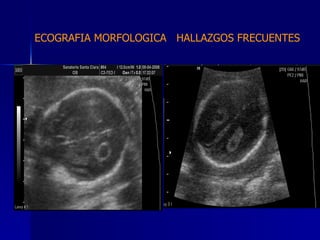

DTFRC-2007 ECOGRAFIA MORFOLOGICA  HALLAZGOS FRECUENTES   SISTEMA NERVIOSO CENTRAL TOTAL  8  26 % 1 HIDROCEFALIA 2 VENTRICULO MEGALIA 4 QUISTE DE PLEXO COROIDEO 1 ANENCEFALIA

DTFRC-2007 ECOGRAFIA MORFOLOGICA  HALLAZGOS FRECUENTES   GENITOURINARIA DISPLASIA RENAL MULTIQUISTICA  3 HIDRONEFROSIS  2 QUISTE DE OVARIO FETAL  1 SISTEMA DIGESTIVO DILATACION INTESTINAL  2  SISTEMA ESQUELETICO   PIE BOT  2  20 % 6 % 6 %